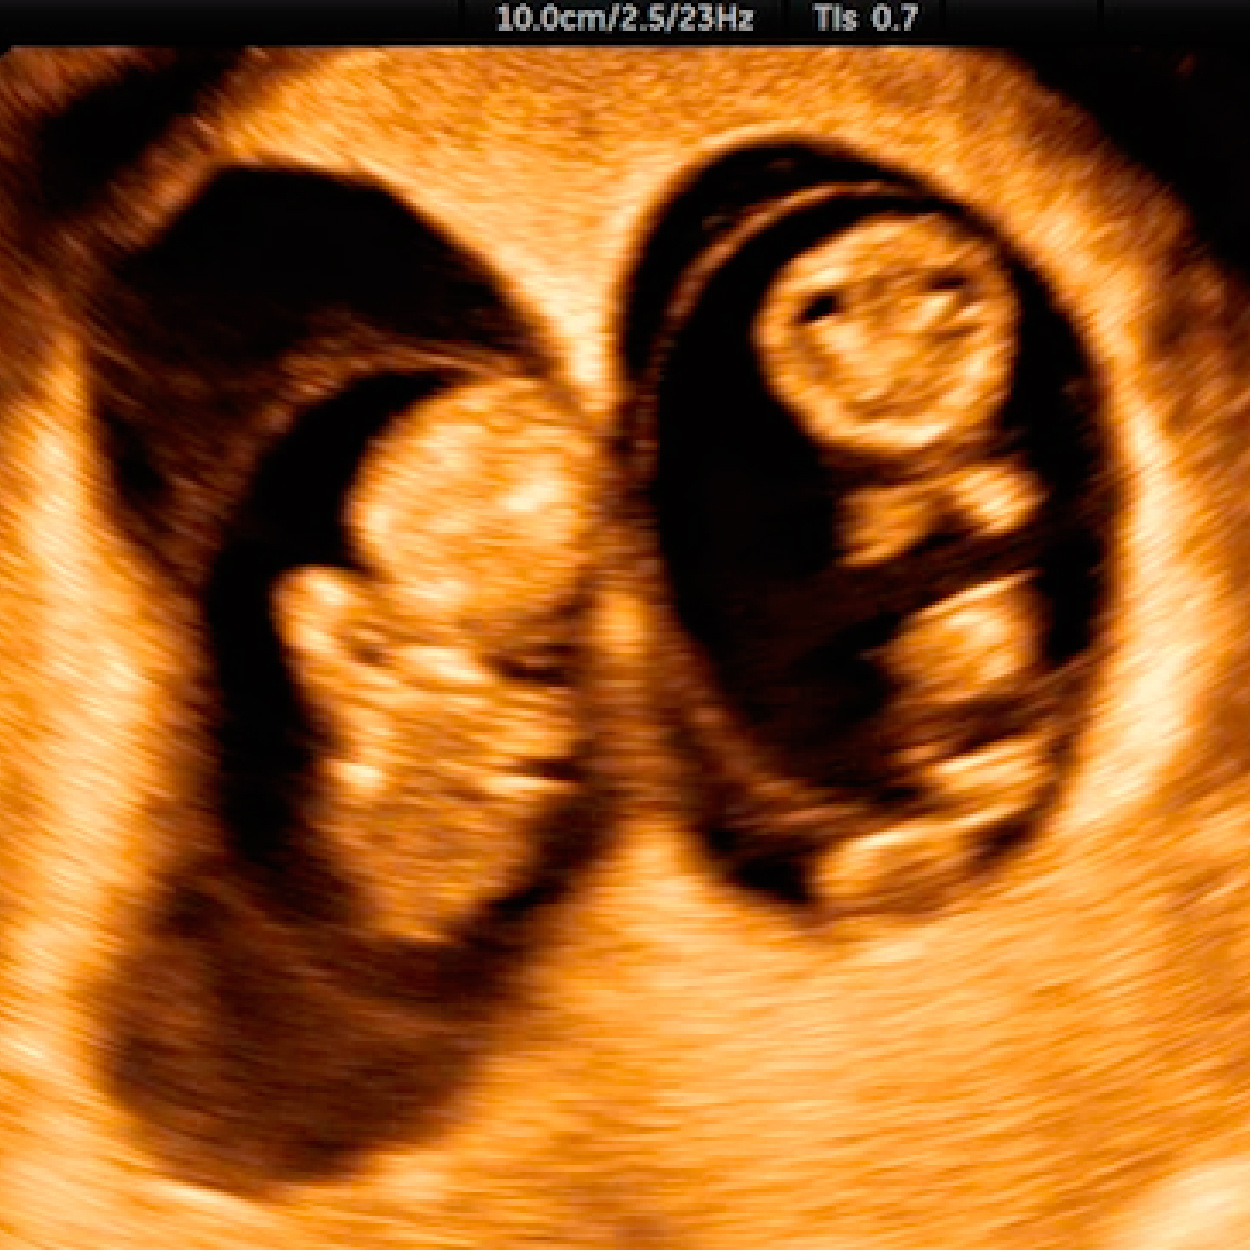

5. Determinar si el embarazo es único o múltiple.